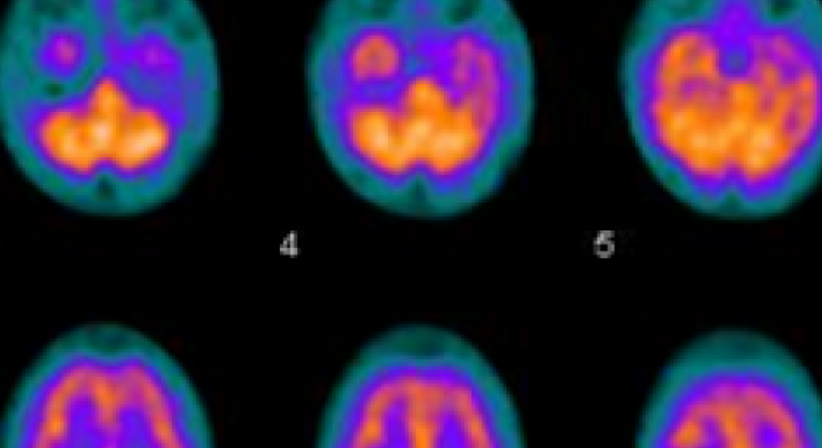

In der Nuklearmedizin werden Spuren von radioaktiven Stoffen (Radiotracer) verwendet, um die Funktion oder die Durchblutung von Organsystemen zu untersuchen.

Wir bieten in unserem Institut folgende nuklearmedizinische Untersuchungen an:

• Schilddrüsenszintigraphie

• Myokardszintigraphie

• Knochenszintigraphie

• Lungenszintigraphie

• Nierenszintigraphie

• Granulozytenscan

• Nebenschilddrüsenszintigraphie